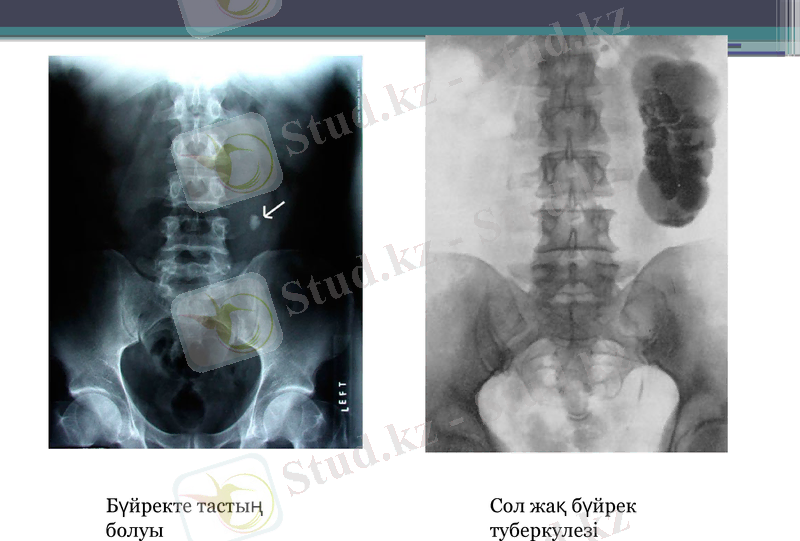

Бүйрек рентгеннограммасы

Қалыпты жағдайда бүйрек көлеңкелері орташа өлшемдері мынадай: ұзындығы 11, 6 ені 6-7. Рентгеннограммада қалыпты бүйректер контуры біркелкі және көлеңкелері гомогенді. Бүйректердің тыныс алу актісімен синхронды, белгілі бір физиологиялық жылжымалылығы бар. Тыныс алғанда болсын сондай бел омыртқасы денесінің ұзындығынан аспауы тиіс. Бүйректердің көрсетілген жылжу диапазонының ұлғаюы оның патологиялық қозғалмалылығын көрсетеді

Бүйректе тастың болуы

Сол жақ бүйрек туберкулезі

Шолу урографиясы

Бүйректер мен қуықтың тік проекциядағы шолыма көрінісі, конкременттерді, жұмыс тіндерге, әк қатуын, газды анықтауға көмектеседі, контрасты зат енгізіп зерттеуден бұрын қашанда жасалуы керек